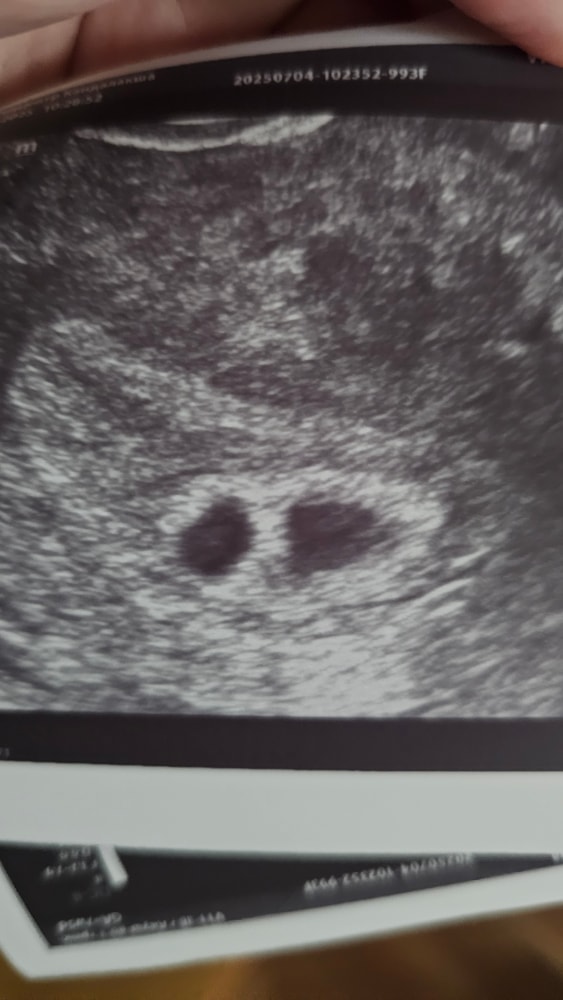

Узи, двойня или гематома? 🤔

Добрый день! Сходила на узи, врач посмотрел, пя в матке, все хорошо, сб увидели🥰 но встал вопрос, сказала сначала отслойка небольшая, гематома образовалась, покой сохранять и не поднимать тяжести. Но смотрит дальше и говорит, а вроде и нет, похоже и на пя, но оно пустое, эмбриона не видно. Поставила на контроль через 10 дней, подтвердить, либо 2 пя и замерло, либо всё-таки гематома, либо 2 пя будет развиваться... У кого были похожие ситуации? Чем закончилось? Живот потягивает иногда, но выделений никаких. Фото прикрепляю

В 1 пя четко видно эмбрион(ктр 6.6), а 2 предполагаемый пя абсолютно пустой

Я не врач, но на мой взгляд это 2 плодных яйца

Похоже на двойню